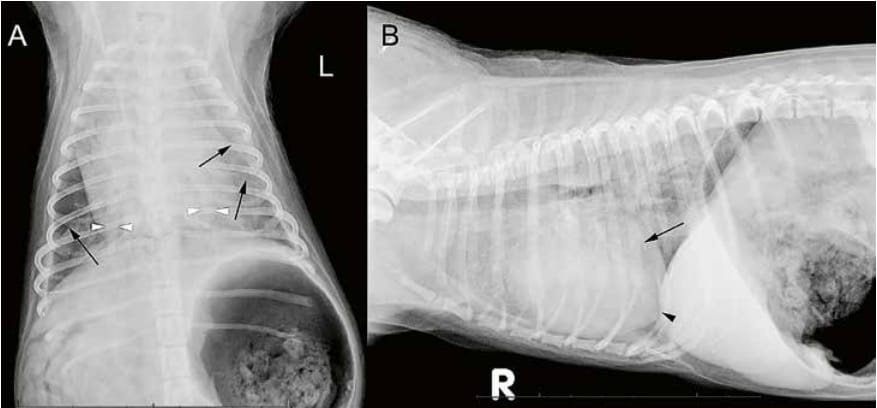

Thoracic radiographs of an 8-year-old intact male Chihuahua in two projections (A: ventrodorsal, B: left to right lateral projection). The images

were taken at the onset of dyspnea two hours after a blood transfusion. A small amount of fluid accumulates in the pleural space, separating the lung

surface from the parietal pleura and causing thin pleural fissure lines (small black arrows). The cardiac silhouette is moderately enlarged. It has a broad

sternal contact and a rounded right side that slightly elevates the cardiac apex (small black arrow head) from the sternum. The left side of the heart

appears small in volume. The caudal pulmonary arteries have a large diameter (white arrow heads). The pulmonary veins are largely masked by a

generalized severe unstructured interstitial lung pattern. The liver has an increased volume and the stomach contains a large amount of gas. The findings were interpreted as non-cardiogenic edema with pressure overload on the right side of the heart, mild secondary pleural effusion and aerophagia.